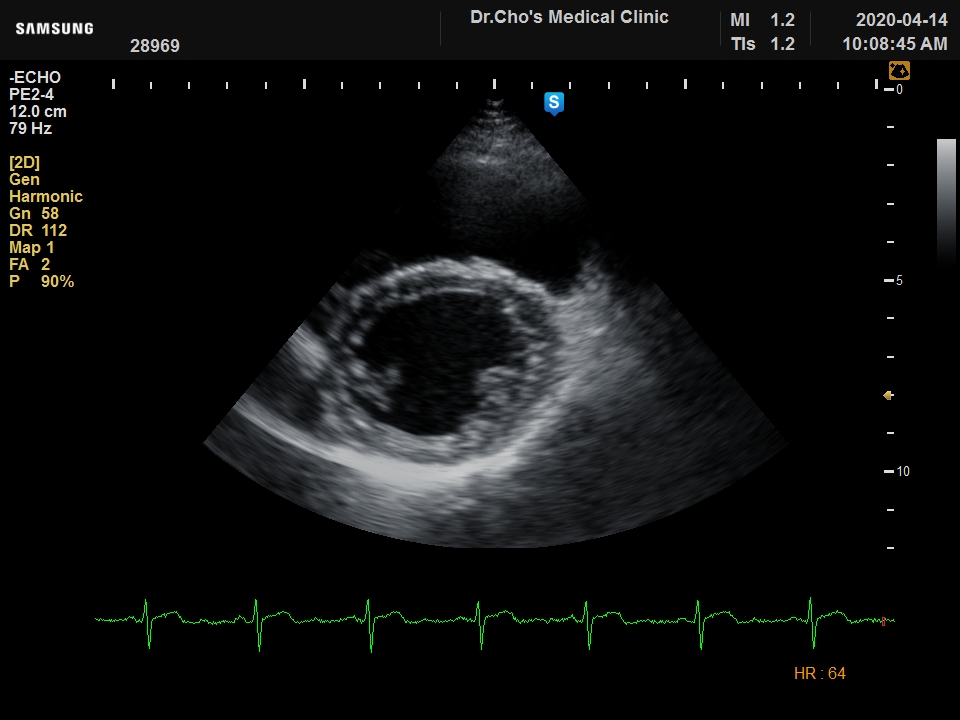

ÃÊÀ½ÆÄ°¶·¯¸®

ºñÈļº ½É...